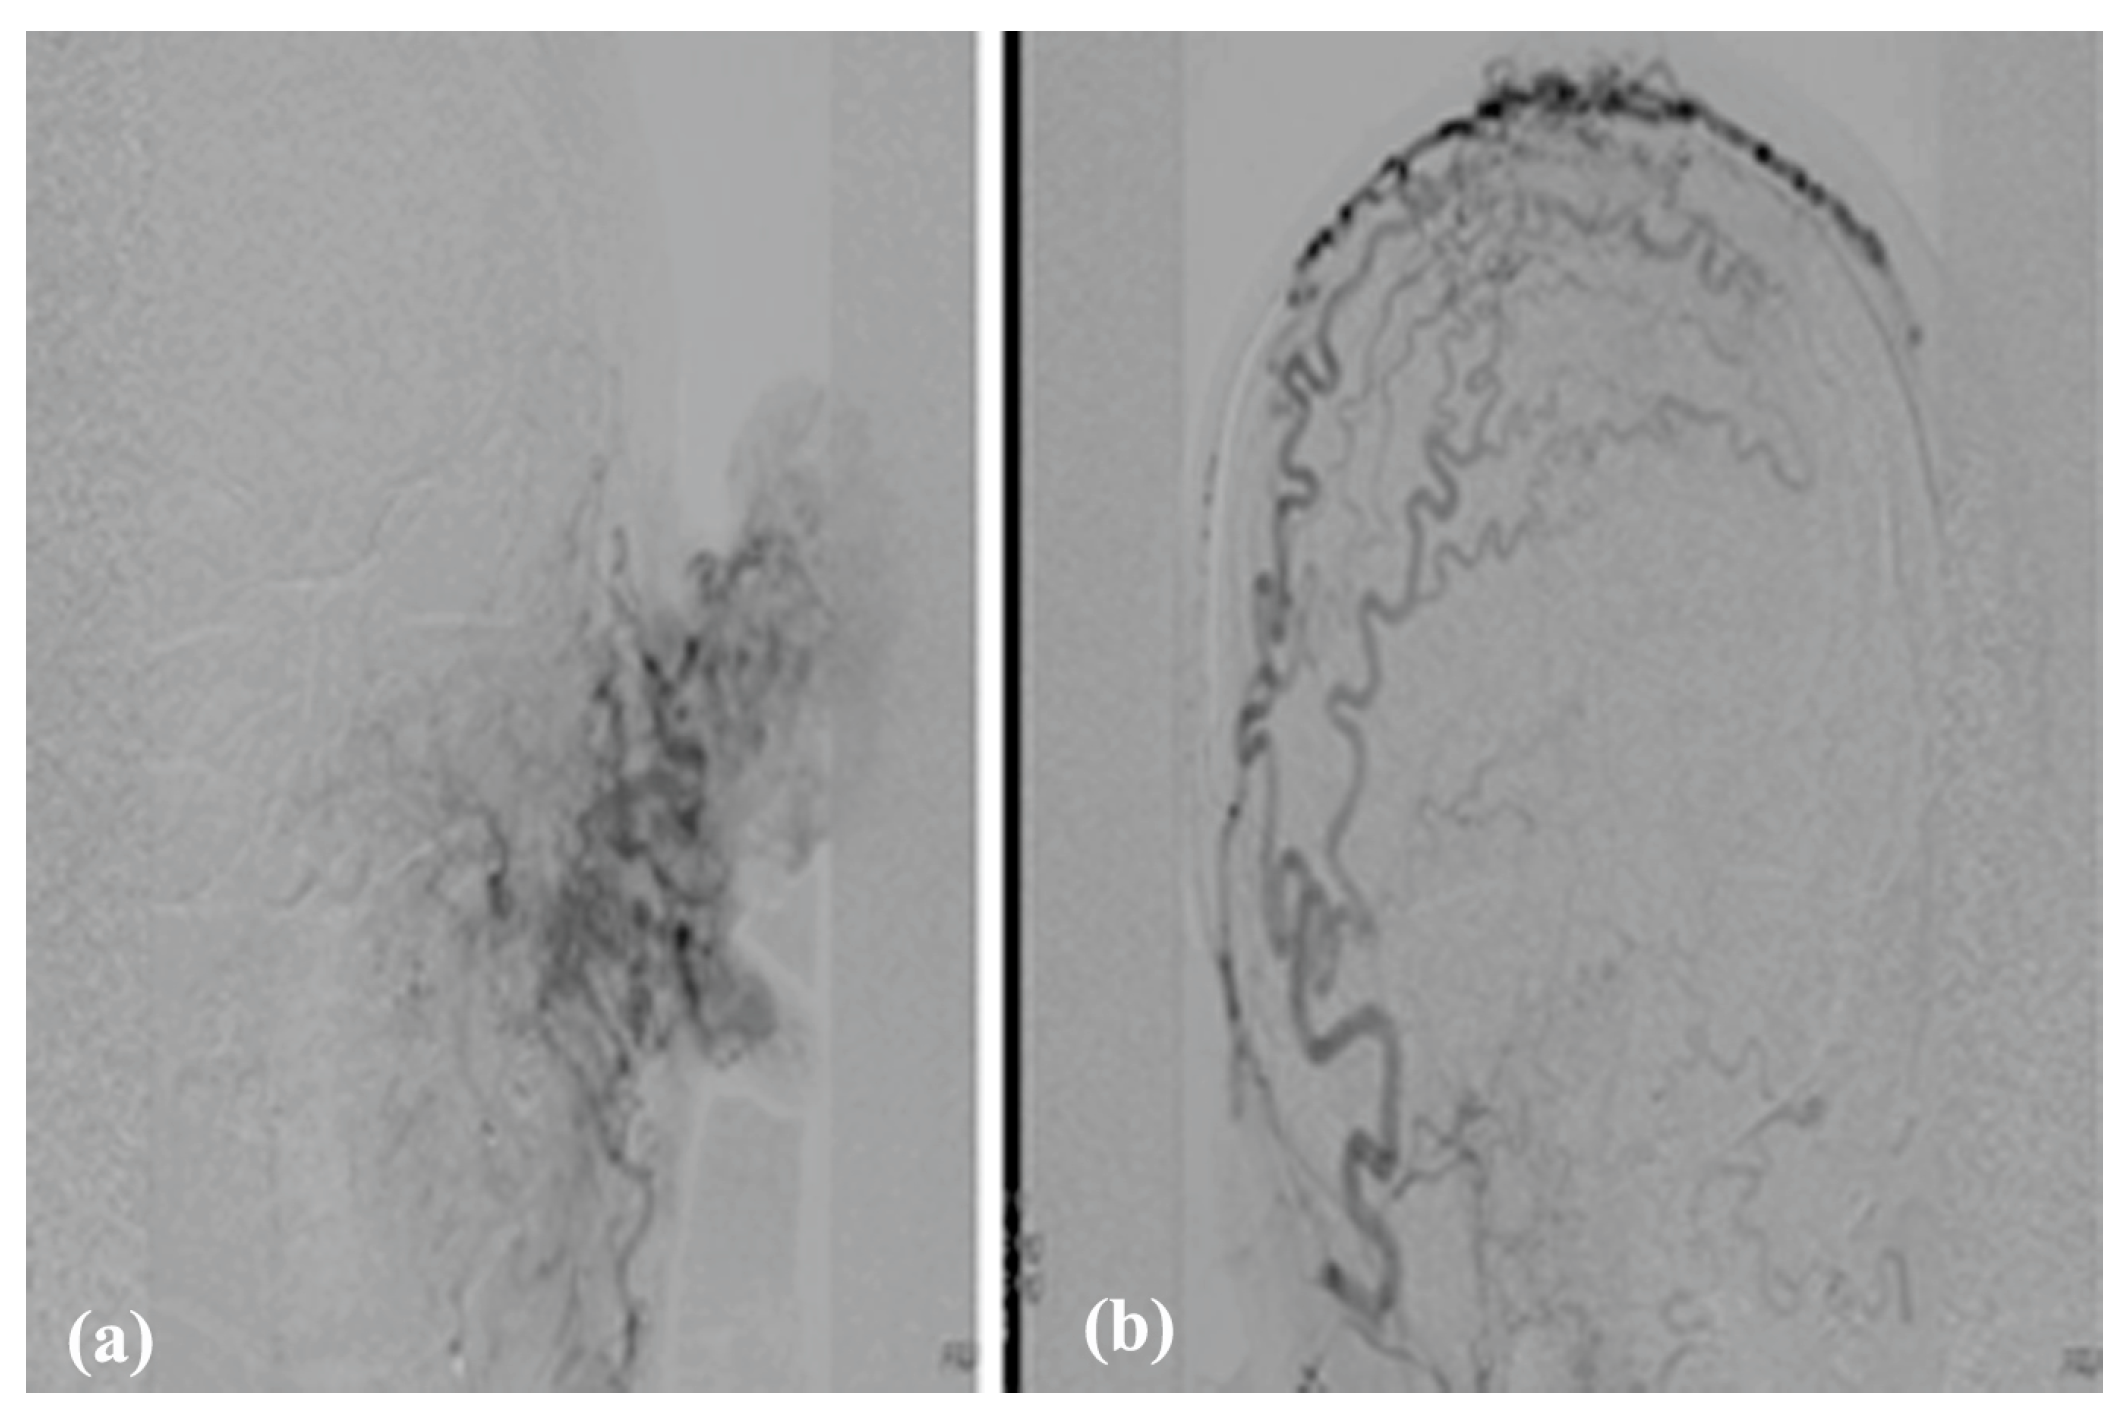

3.3. Arteriovenous Malformations

3.3.1. Clinical Data

3.3.2. Diagnosis

3.3.3. Therapy